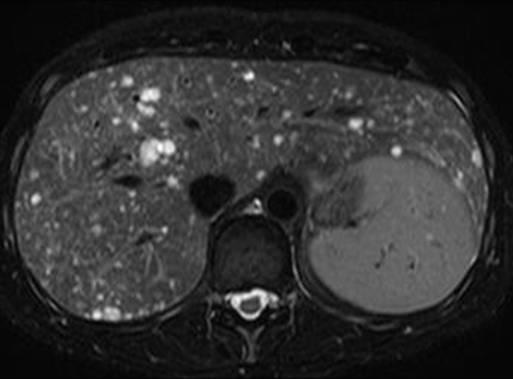

Hamartoma đường mật

» Thông tin: Nam giới – 34 tuổi.

» Lâm sàng: Kiểm tra sức khỏe.